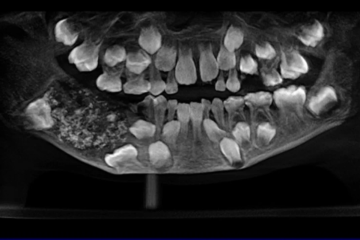

Atendido no Saveetha Dental College and Hospital, o menino se queixou de inchaço do lado direito da mandíbula, além da não erupção dos dentes permanentes. Após fazer tomografias e radiografias, o problema foi constatado: uma densa massa de 200 gramas estava alojada na mandíbula inferior.

A abertura do material, já em laboratório, revelou ainda mais desdobramentos. Dentro da massa, antes na mandíbula inferior, 526 estruturas ósseas, semelhantes a dentes, foram encontradas. Variáveis entre 0,1 mm e 15 mm, possuíam raiz, coroa e até esmaltem, justamente características de dentes verdadeiros.